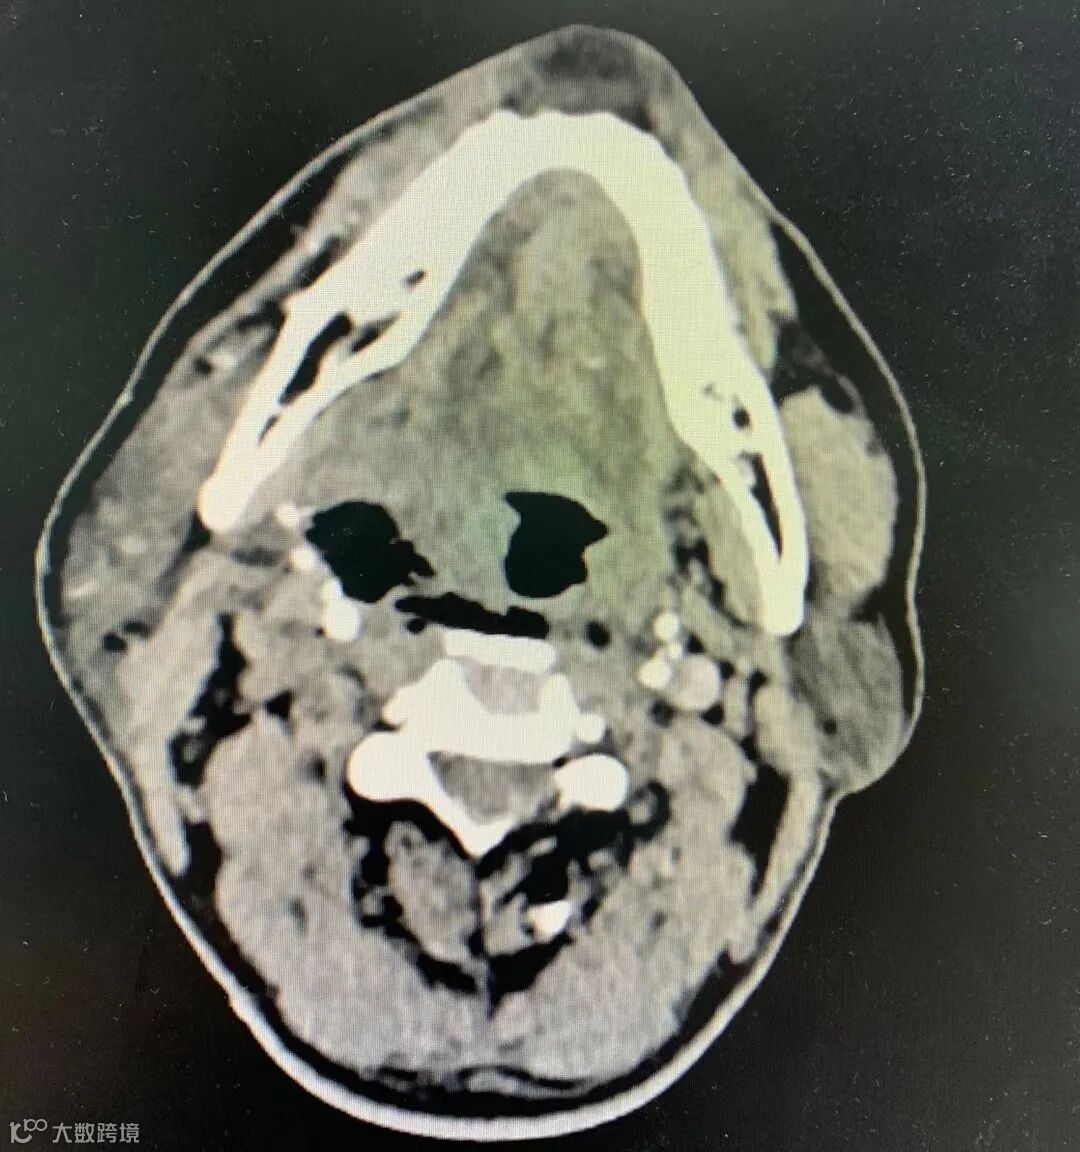

6月29日,广西百色的陆先生上树摘果时不慎坠落,被一截14厘米长的树枝穿颈而入,情况十分危急。

树枝扎入的位置虽然紧邻颈血管鞘,紧紧擦着血管壁扎入,但未刺破颈鞘内的大血管,也并未伤到颅脑,患者还合并左侧胫腓骨下端粉碎性骨折。医生最担心的是松解后出现颈总大动脉破裂大出血。医务部迅速组织多学科团队会诊,制定了周密的手术方案。

14厘米的树枝穿通颈部触及颅底后受力已经弯折,紧贴着血管颈内静脉和颈总动脉,而且插入的位置很高很深尖端上抵颅底,外侧又有下颌骨阻挡,操作空间很有限。连耳鼻咽喉外科特有的电刀和钳子都难以伸进去止血。如果出现颈动脉大出血,后果不堪设想。麻醉科利莉副主任医师首先为患者打开气道,保证呼吸畅通,开通深静脉通道,为可能出现的大出血抢救做好准备。

术中,张哲带领手术团队沿着树枝入口处皮肤做T形切口,充分暴露分离颈内静脉和颈总动脉,并用标识带预结扎。然后小心翼翼地把树枝周围肌肉分离松解,一直到近颅底处树枝末端附近。张哲将嵌顿的树枝充分松解后,迅速将其拔出,并快速止血。